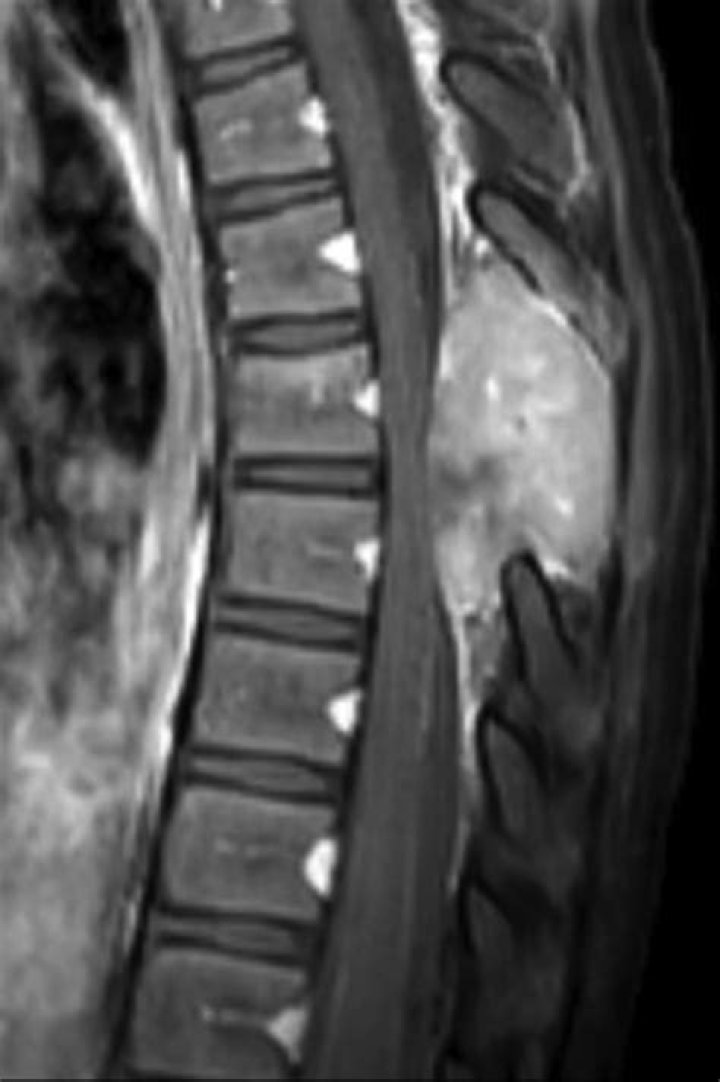

Neck pain is the most common presenting symptom of patients with a cervical spine tumor. Patients often have unrelenting pain, as well as night pain, that...